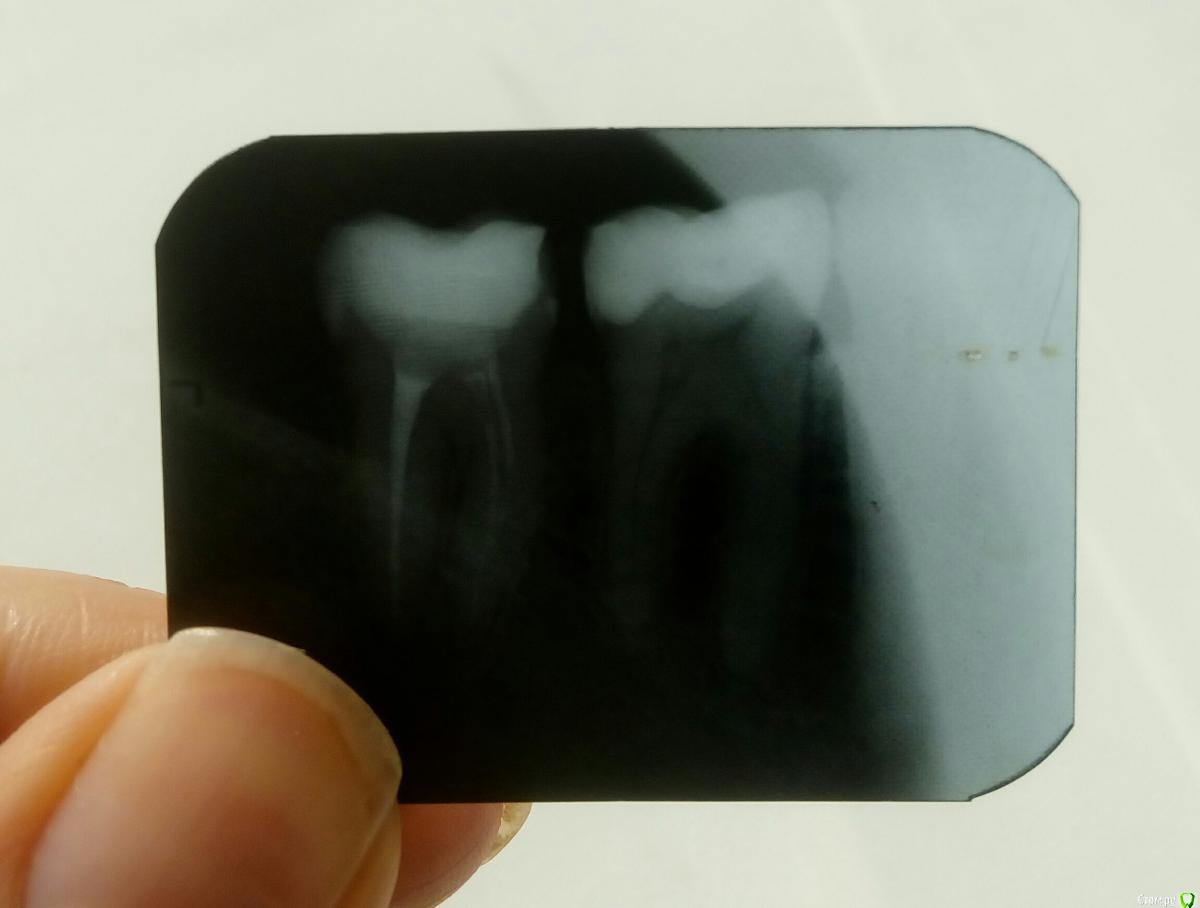

Lentyaika Опубликовано 10 октября, 2017 Автор Поделиться Опубликовано 10 октября, 2017 Снимок.. Ссылка на комментарий

red_butler Опубликовано 10 октября, 2017 Поделиться Опубликовано 10 октября, 2017 Снимок.. для начала хорошо бы сделать новый снимок, и провести ревизию корневых каналов 2 Ссылка на комментарий

chervoncevdaniil Опубликовано 10 октября, 2017 Поделиться Опубликовано 10 октября, 2017 (изменено) Снимок.. Может конечно вы с доктором немного друг друга не понимаете,но если док просто хочет оставить такую пломбу и накрыть это коронкой,то я боюсь это не очень хороший вариант.Плюс соглашусь с red_butler,есть вопросы к пломбировке каналов,но опять же качество снимка не супер,чтобы сказать на 100% Изменено 10 октября, 2017 пользователем chervoncevdaniil 1 Ссылка на комментарий